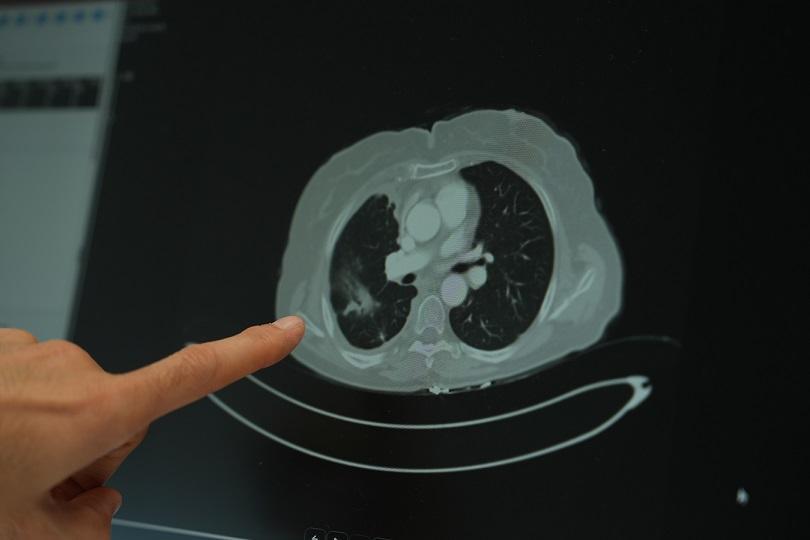

Ailesinde kanser öyküsü bulunan gençlerin çok daha dikkatli olması gerektiğini vurgulayan Doç. Dr. Şimşek, “Ailede kanser varsa, tarama yaşları çok daha genç yaşlara çekilebiliyor. Bazı durumlarda 18-20 yaşlarından itibaren düzenli kontrollerin yapılması hayati önem taşıyor” diye konuştu. Sigara kullanımının akciğer kanseri üzerindeki etkisini değerlendiren Doç. Dr. Şimşek, uzun süre sigara kullanan kişilerde düşük doz radyasyonla yapılan tomografi taramalarının önerildiğini belirterek “Sigara içen bireylerde akciğer kanseri riski yüksek. Bu nedenle düşük doz radyasyonlu taramalar, erken tanı açısından önemli” ifadelerini kullandı.